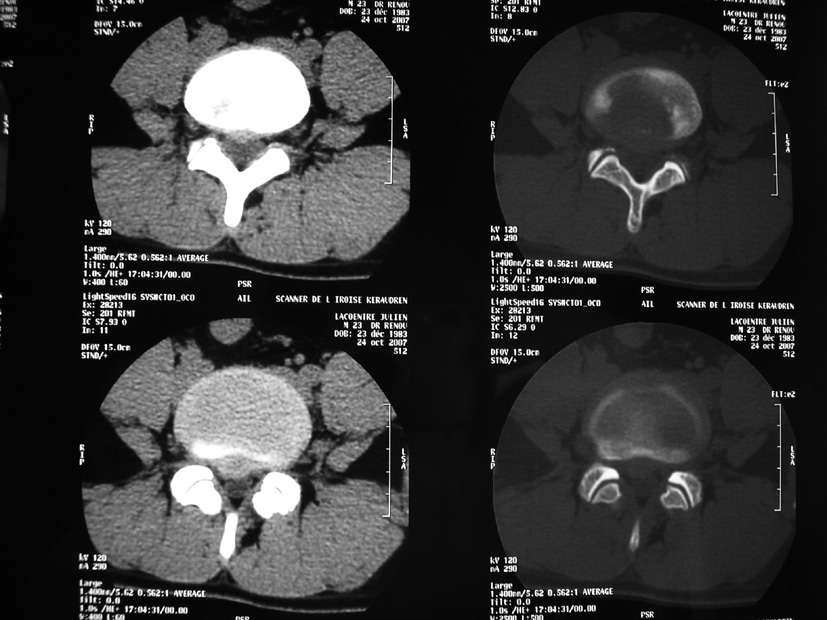

Monsieur B., quarante-quatre ans, professeur de mathématiques, sans antécédents, vient vous consulter pour une lombalgie irradiant dans le membre inférieur gauche. La douleur lombaire est apparue il y a quinze jours après un effort de soulèvement. Il s’agit d’une douleur lombaire basse, relativement supportable, irradiant à la face postéro-externe de la cuisse, à la face externe de la jambe et au dos du pied. La douleur est aggravée par les efforts, soulagée par le repos, impulsive à la toux.Son seul antécédent est une malposition urétérale opérée dans l’enfance. L’examen clinique montre un signe de Lasègue à gauche à 55°, une colonne lombaire enraidie et douloureuse à la palpation. Il n’y a pas d’anomalie à l’examen neurologique, pas de fièvre, pas d’altération de l’état général. Il vous apporte ses radiographies et son scanner qui explore L5S1 et L4L5 (clichés ci-dessous).

Décrivez l’image scanographique. Est-elle compatible avec le tableau clinique ?